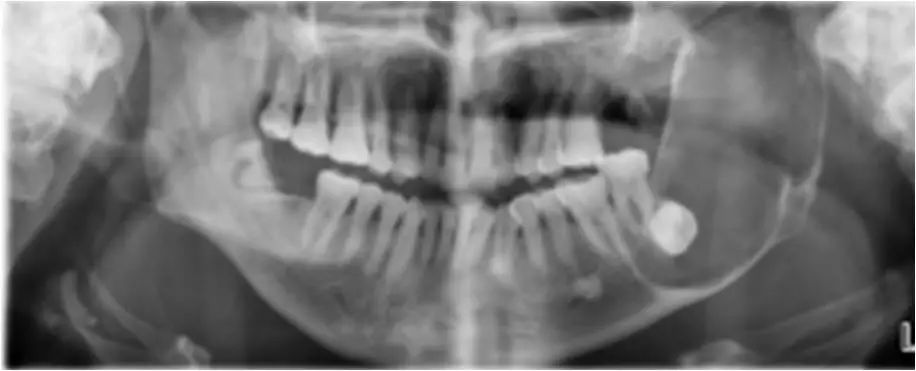

04 咀嚼肌间隙、颌下间隙、左侧颞下间隙,颊间隙,翼颌间隙

男,55岁,左下后牙反复肿疼1年余,加重1月余,疼痛剧烈伴张口受限,面部肿胀。

咀嚼肌间隙有脓肿形成。